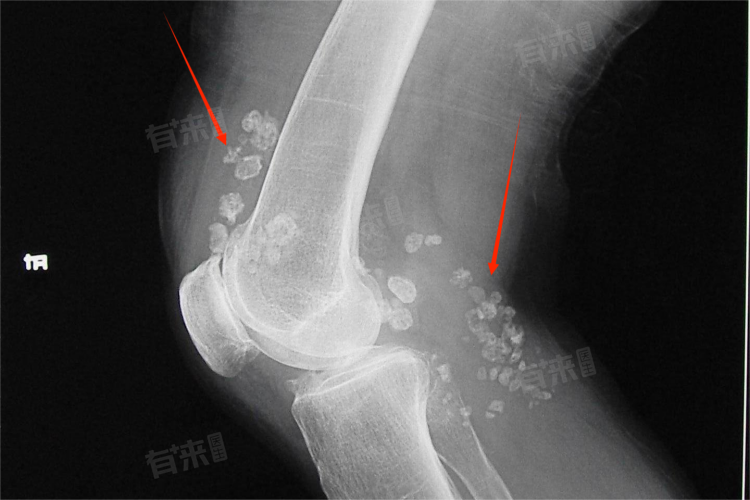

- 当滑膜软骨瘤导致关节功能严重受限,如关节活动范围明显缩小、关节卡顿、行走困难等,应尽快进行手术,长时间的关节功能异常会进一步加重关节的损害,甚至可能导致关节畸形等不可逆的后果,手术的目的不仅是切除肿瘤,还包括恢复关节的正常结构和功能,手术的紧迫性较高,不宜拖延。